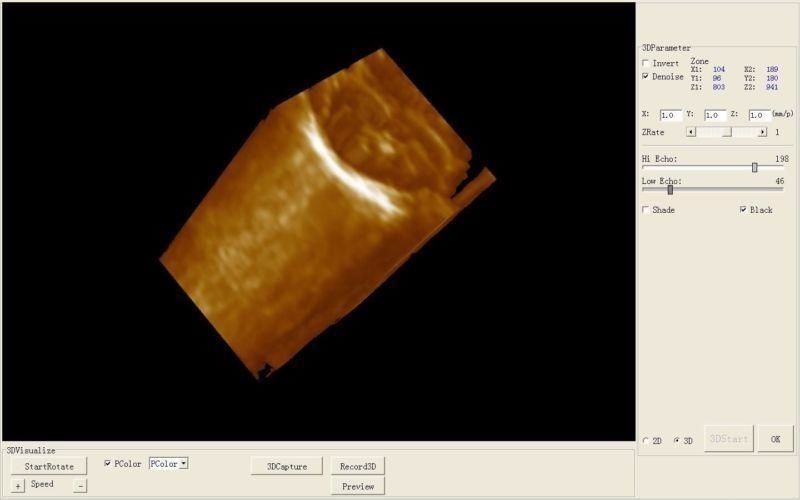

Comprehensive Diagnostic Capabilities

The Laptop Ultrasound Scanner is designed to provide clear and precise imaging, making it an essential tool for healthcare professionals. This device offers advanced functionality, allowing doctors to perform a wide range of examinations. Because it includes a transvaginal probe, it is particularly effective for gynecological assessments, ensuring accurate diagnosis.

The Laptop Ultrasound Scanner is equipped with an intuitive interface that simplifies operation. Even those who may not be tech-savvy will find it easy to navigate through various functionalities. Additionally, the visual output on the laptop screen is clear and informative. So, both experienced and novice users can quickly learn how to use the device effectively.